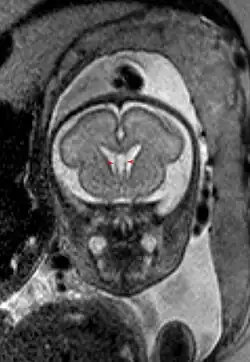

Cavum septi pellucidi beim Fetus als Normalbefund in der pränatalen Kernspintomographie.

Das Cavum septi pellucidi ist eine normale anatomische Struktur in der Entwicklung des Feten, die beim Erwachsenen in der Regel zurückgebildet bzw. obliteriert ist. Man findet das Cavum septi pellucidi noch bei praktisch allen Frühgeborenen, bei 85 % normaler Neugeborener und in 1 bis 20 % noch bei Erwachsenen. Ein Cavum vergae zeigt sich bis zum 6. Monat ebenfalls bei 100 % der Feten und bei 30 % der normalen Neugeborenen. Bei Erwachsenen wird eine Häufigkeit von weniger als 1 % angegeben.